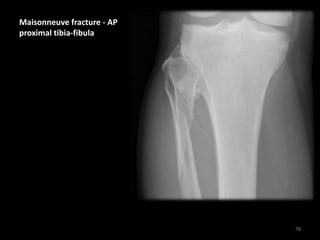

Maisonneuve fracture - AP

proximal tibia-fibula

Spiral fracture of the

proximal fibula